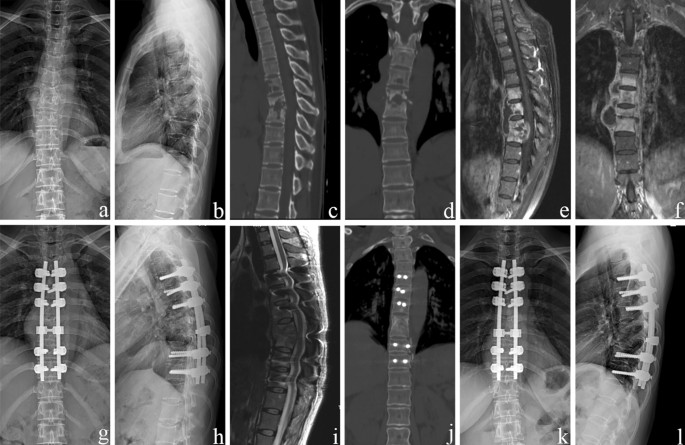

The average preoperative thoracic kyphosis angle was 34.4° ± 4.5°, which decreased to 22.0° ± 2.6° postoperatively. At the final follow-up, the mean deformity angle was 23.7° ± 2.1°, with only a 1.7° ± 1.1° correction loss (p < 0.05). Single-level debridement and interbody fusion were performed in 28 patients, and two-level procedures were completed in 14 patients. Spontaneous intervertebral bone fusion was achieved 10.6 ± 2.1 months after surgery (Table 2). No nonunion, pseudoarthrosis, loosening, or breakage were observed at the final follow-up (Figs. 3 and 4).

A 49-year-old female demonstrating lesions received a one-stage posterior transforaminal thoracic debridement, interbody fusion, and instrumentation. (a–f) Preoperative radiographs, CT, and MRI scans show TB of T5–T8 with vertebral bone destruction and deformity (kyphosis angle 36°) and paravertebral abscess formation. (g,h) Postoperative radiographs demonstrate the correction of the deformity (kyphosis angle 23°). (i) Postoperative MRI that shows clearance of TB lesions and spinal cord decompression. (j) CT shows satisfactory bone fusion at 12 months. (k,l) Radiographs display good internal fixation position and solid bone fusion, with a correction loss of 1° after 81 months of follow-up.